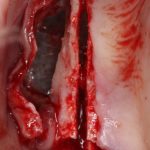

Разрез.

На этапе разреза делают дофига ошибок, что приводит к излишней травматичности вмешательства, сложностям при ушивании раны, расхождению швов и т. д. В общем, к нему нельзя относиться пофигистически.

За редким исключением, мы всегда проводим разрез в пределах прикрепленной десны. Даже если её участок шириной всего полтора-два миллиметра — постарайся оставить его в этих границах.

Поскольку мы планируем получать аутотрансплантат из этой же области, мы продляем разрез до донорской зоны. В этом участке удобно вывести его вестибулярно, прямо в проекции наружной косой линии.